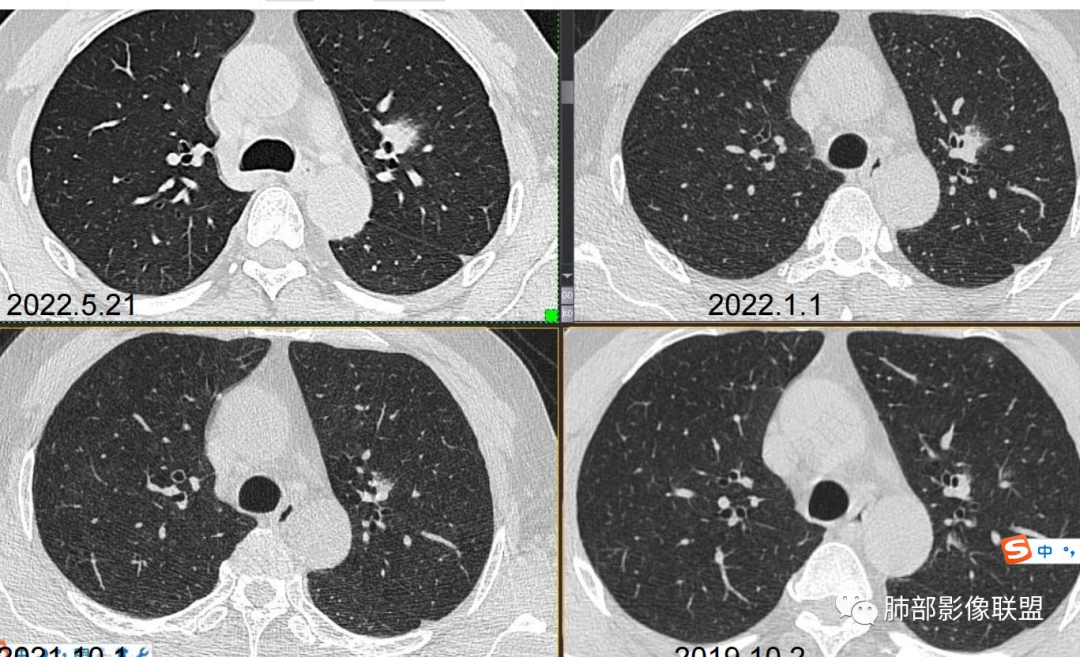

中老年男性,左肺上叶中轴区实性结节及周围磨玻璃影,磨玻璃边界似清非清,关键点2019.10-2021.10-2022.05结节持续增大,增强后明显强化。考虑恶性结节可能大,腺癌(黏液腺癌)?鉴别炎性结节。

左肺上叶前段实性结节,沿支气管血管束生长,整体形态近三角形,边缘模糊,累及前段气管主支管壁增厚,管腔通畅,前后复查不足两年病灶倍增明显,肿瘤指标阴性,支持炎性肉芽肿,2019年10月2日首诊图,主体结节外周似有小卫星灶分布,需薄层确认,支气管镜肺泡灌洗检查。

57岁,属于高危人士;病灶3年逐步增大,肿瘤按理是要考虑的

初始病灶应该是这里

病灶朝前、外侧进展

1、临床:57岁男性,3年逐步增大。孤立病灶持续三年原地坐大,符合肿瘤性病变,恶性程度不高或者早期进展缓慢。良性肿瘤常多年静止或进展极其缓慢。炎性病灶“星火”可以燎原,临床表现也会逐步加重。尽管继发性肺结核可以相对惰性,但病灶强化不明显,多结节、多卫星、多新旧不等,相对清楚硬朗。

2、病灶以实性密度为主,前、外侧蔓延,GGO部分边界清楚,部分欠清

1、连续3年观察,病灶逐步增大,符合惰性恶性肿瘤。2、支气管壁增厚,腔内内壁无变化——病灶长轴沿支气管周围蔓延;朝外走,内侧没有,提示病灶间质为主,与支气管无关。

3、GGO长期存在,朝外蔓延,支持恶性特点。